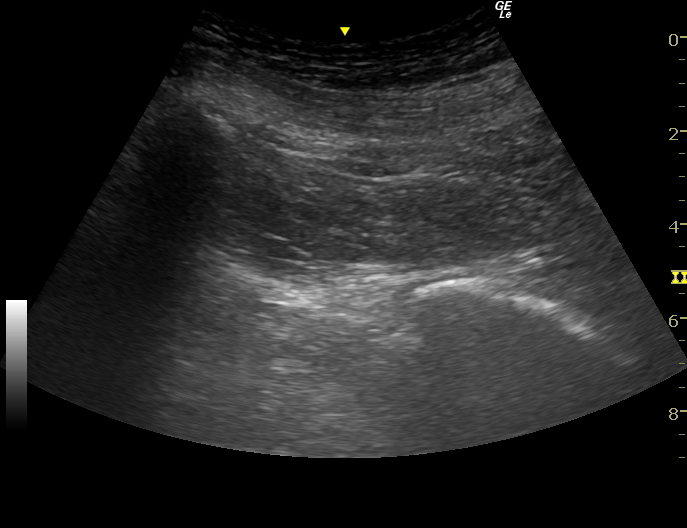

ファシアリリース・筋膜リリース・神経リリースは神経ブロックとは違いますが、エコーを使用して結合組織、筋膜、神経周辺に生理食塩水などを注入し、痛みやコリを治療するものです。エコーで見ると筋肉の筋膜以外にも、腱や靭帯、脂肪などにも白く厚く重なった癒着した組織が発生します。そこが痛みの原因となったり、組織間の滑走性が低下し可動性が制限されたり、血液の流れが悪くなっている可能性があります。

実際のファシアリリースの動画(再生ボタンを押してください)